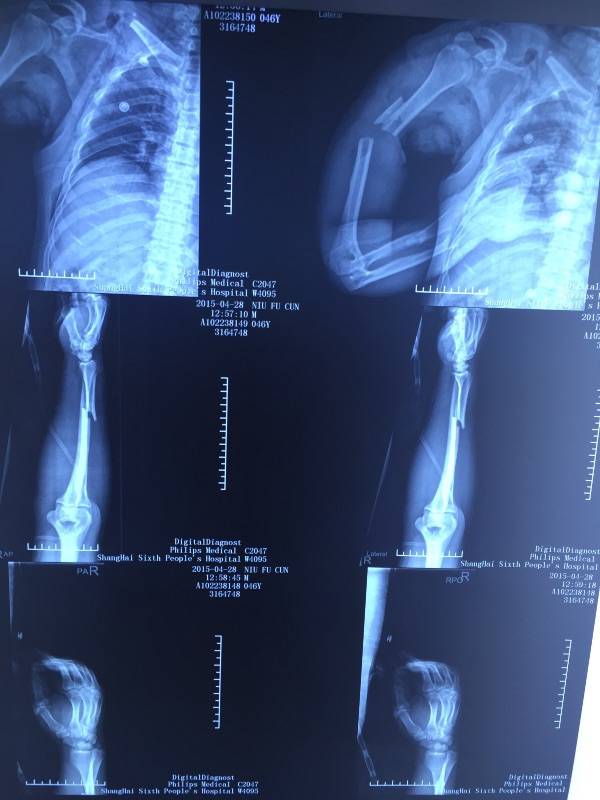

[断指再植] 肩胛带离断再植一例

肩胛带离断,再植风险很高,由于肢体肌肉多,出现肾功能损害几率增加。高手!

期待术后